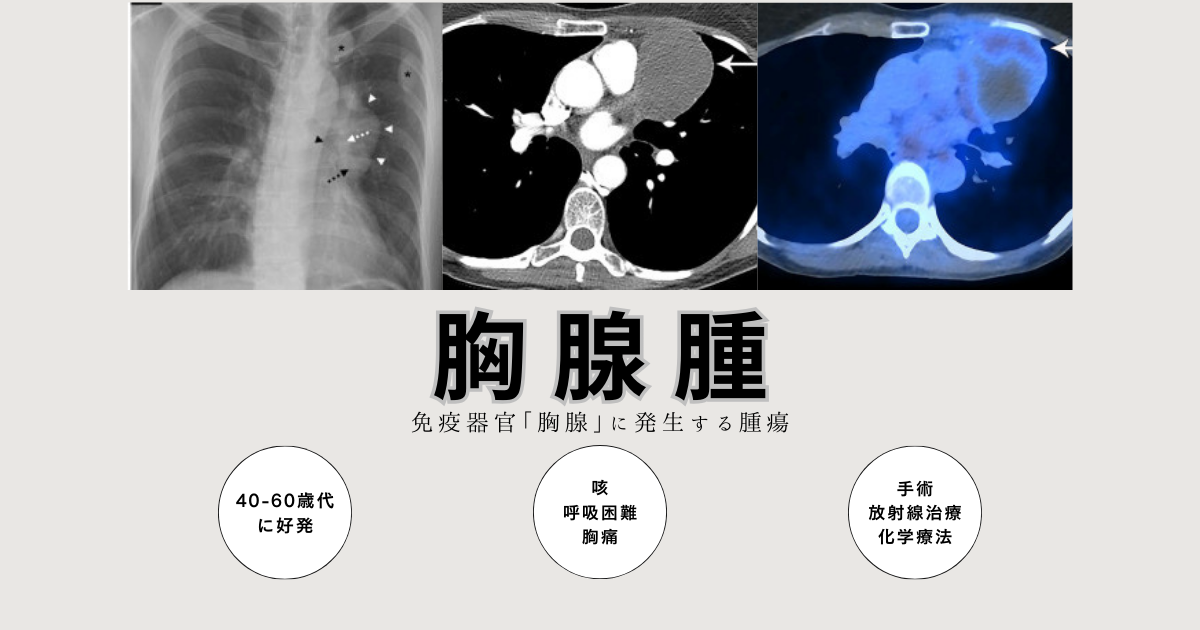

日本全国送料無料商品人気ランキング 胸腺腫(きょうせんしゅ 神戸きしだ - 呼吸器疾患 – Thymoma) 健康・医学の詳細情報

胸腺腫(きょうせんしゅ Thymoma) – 呼吸器疾患 - 神戸きしだ。Nerves of the Thorax: Atlas of Normal and Pathologic。胸腺腫(きょうせんしゅ Thymoma) – 呼吸器疾患 - 神戸きしだ。2024年度 新潟県魚沼産BLコシヒカリ10kg。Thoraco-abdominal CT scan. A shadow (90 mm in diameter) can。数ページ鉛筆による書き込みあり